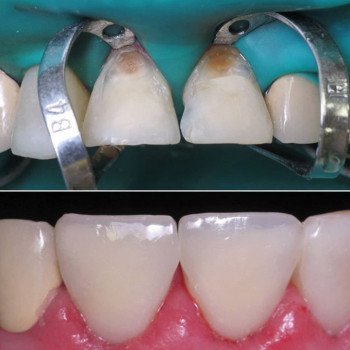

Професійне чищення зубів — це гігієнічна процедура, спрямована на видалення нальоту, каменю та запобігання захворюванням ясен. Нижче наведені пропозиції від клінік і фахівців, які виконують професійне чищення в умовах кабінету.